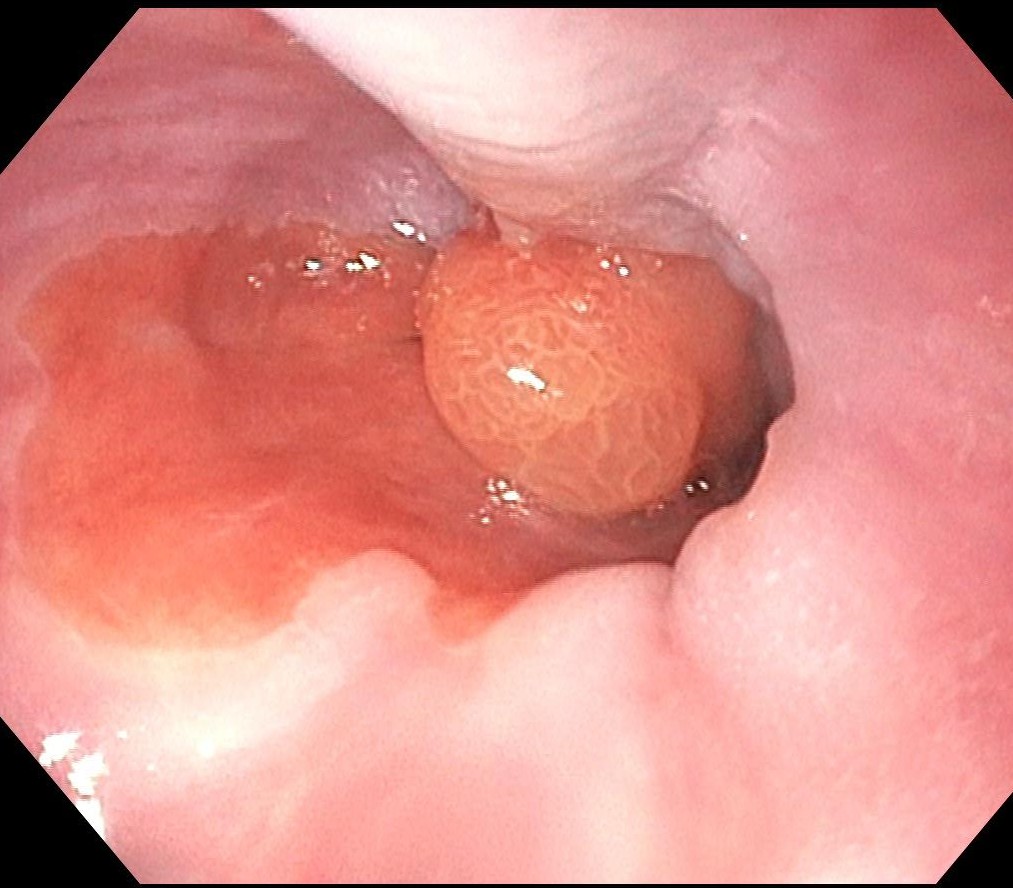

嚥下障害を有する患者さん:内視鏡観察では食道胃接合部にショートバレット粘膜とその境界に腫瘍を認めます。

NBI(狭帯域光観察)では悪性所見は認めませんが、有症状のため、治療適応と診断しました。

嚥下障害を有する患者さん:内視鏡観察では食道胃接合部にショートバレット粘膜とその境界に腫瘍を認めます。

NBI(狭帯域光観察)では悪性所見は認めませんが、有症状のため、治療適応と診断しました。